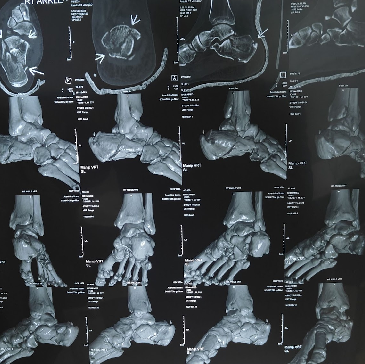

Foot and Ankle Surgery in Perambur

Foot and ankle surgery may be used to address problems involving bones, joints, ligaments, tendons, and soft tissues.

- Fractures and malalignment following injury

Doctors typically review your history and symptoms, then use clinical examination and imaging (such as X-ray and/or other scans) to understand the underlying cause and plan the procedure.